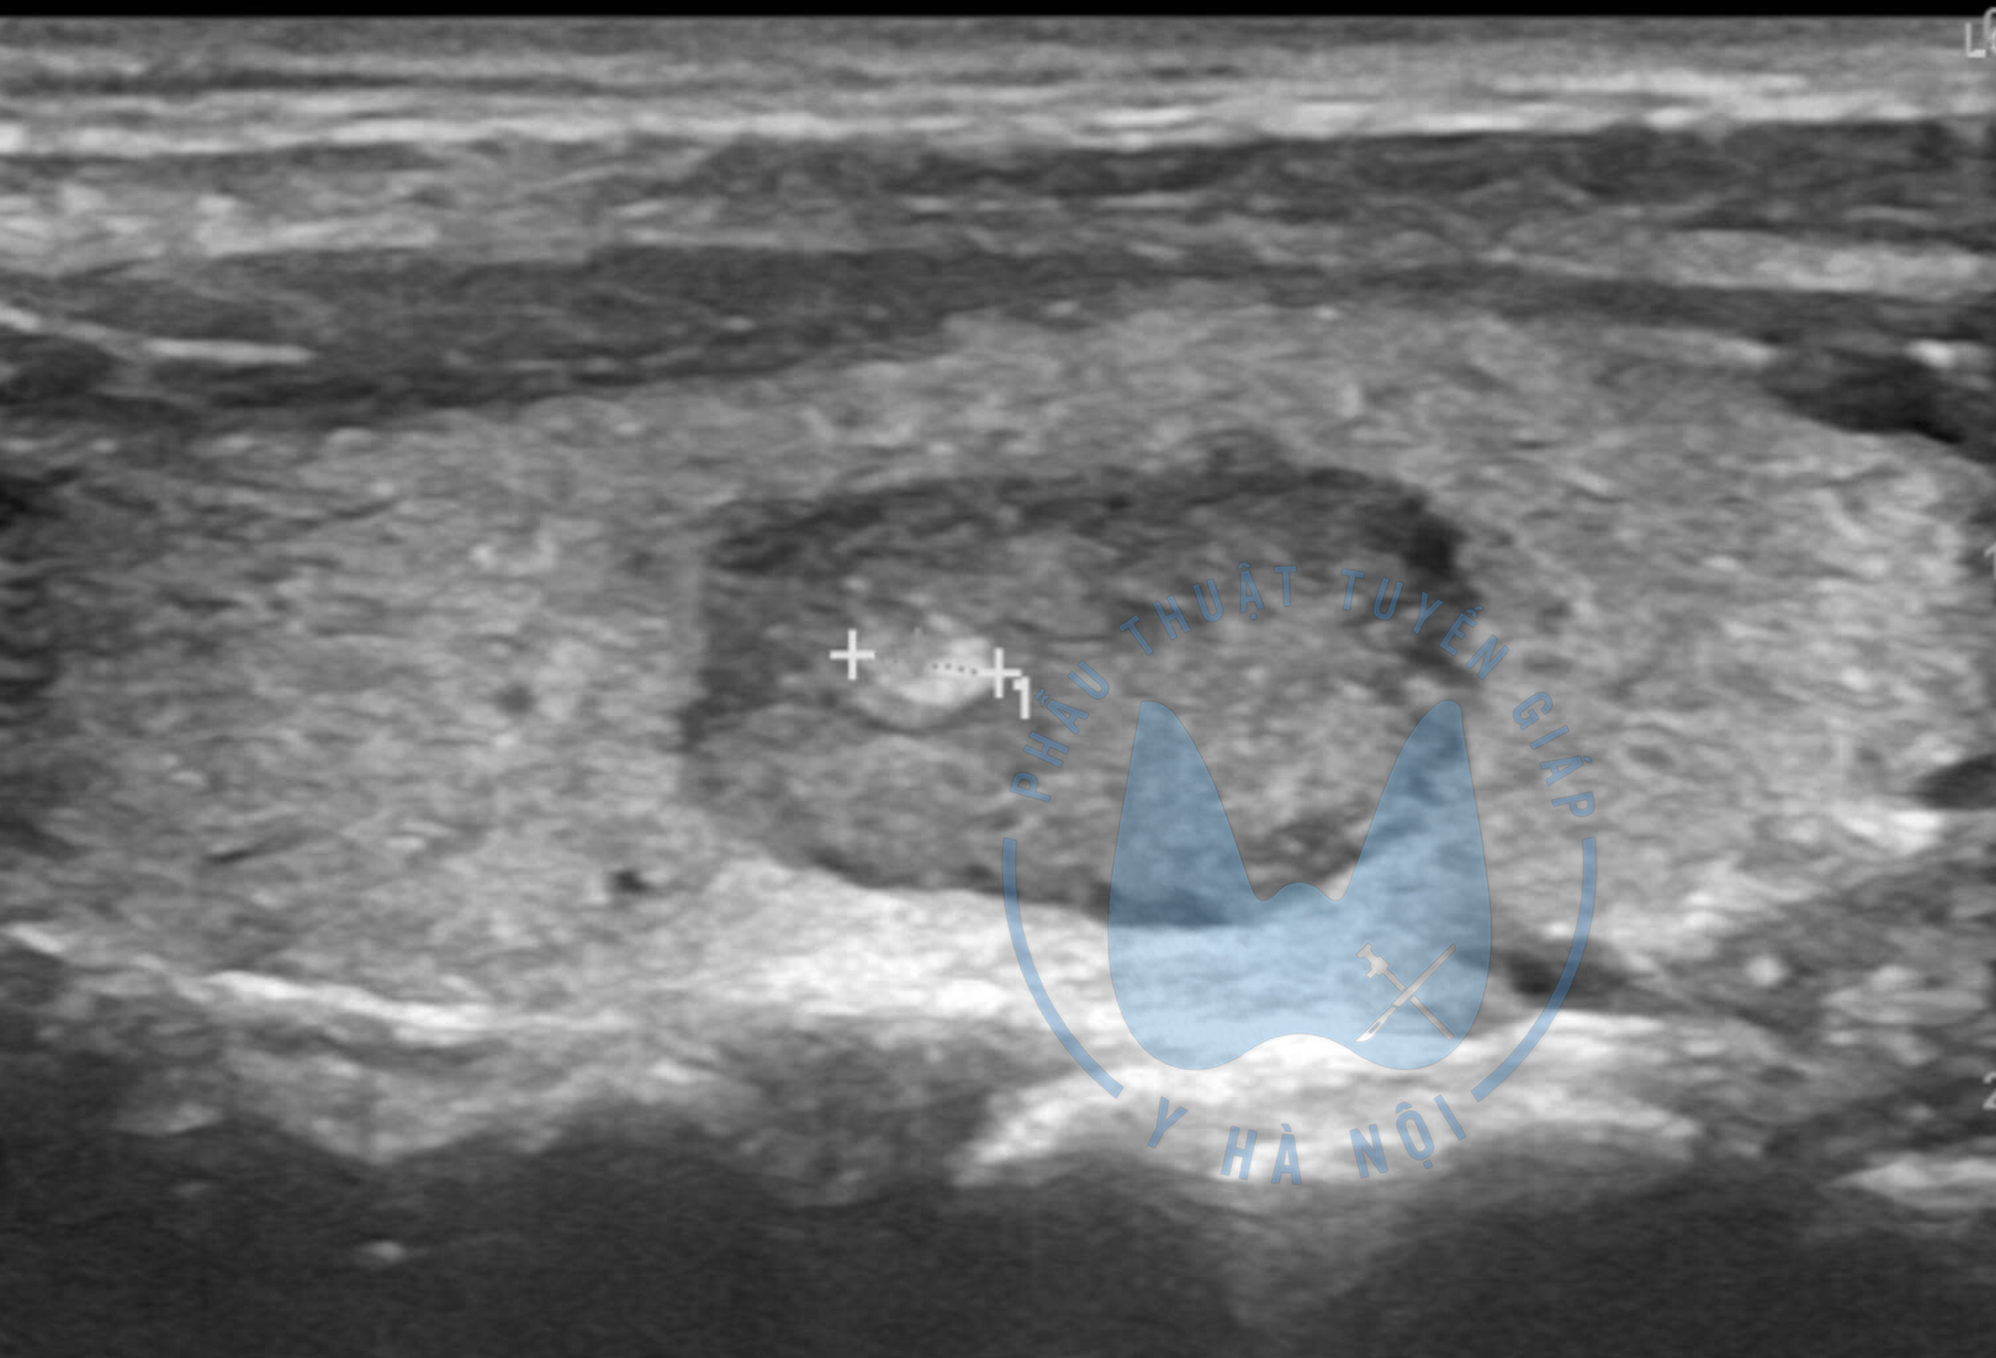

- Siêu âm tuyến giáp: giúp đánh giá hình thái, kích thước, nhưng không đủ chính xác để kết luận.